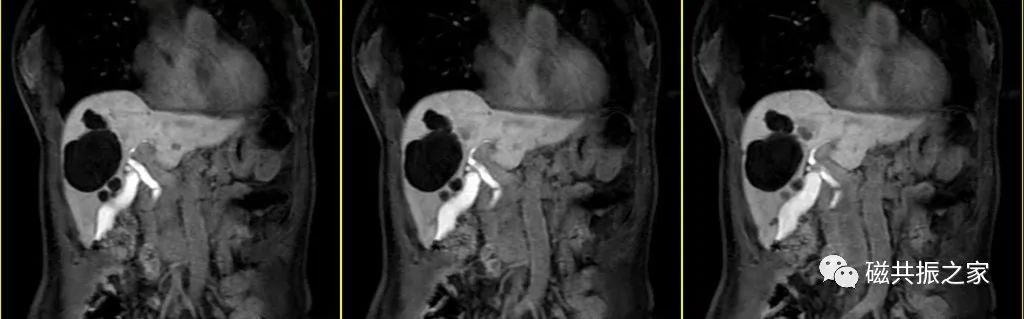

冠状位:冠状位平衡期/延迟期增强补充序列

在横轴位及矢状位上定位,范围包括整个肝脏及病变范围。

大范围的冠状位增强序列有助于对血管、胆管、十二指肠区域以及周围受累情况的评估,